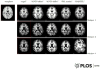

Magnetic resonance imaging (MRI) has led to the identification of widespread brain abnormalities in multiple sclerosis (MS) that extend far beyond the classic white matter lesion. These findings have generated the idea that MS should be understood as a disease of the whole brain, not just the white matter. While it is no doubt the case that many different pathways are ultimately involved in the destruction of brain tissue that occurs in MS, the implications of the accumulated evidence for understanding disease pathophysiology - and hence the overall significance of these imaging findings - are doubtful. Here, I argue that the principled use of imaging can, in fact, address questions about the genesis of these whole-brain abnormalities, rather than simply describe them.